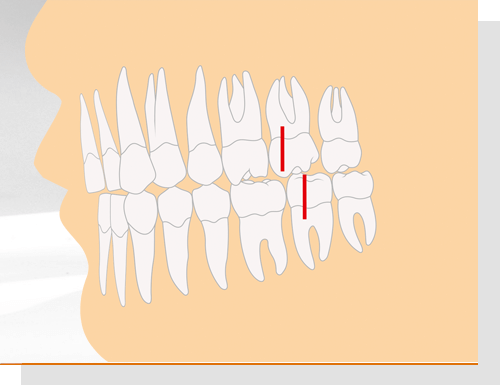

Angle-Klasse 1

Damit wird ein normales Gebiss beschrieben (Neutralbiss): Der vordere Höcker des ersten großen Backenzahns im Oberkiefer trifft genau zwischen die beiden Höcker des gegenüberliegenden ersten großen Backenzahns im Unterkiefer. Nicht nur die Zähne von Ober- und Unterkiefer beißen an den korrekten Stellen aufeinander. Auch das Gesichtsprofil wirkt harmonisch.